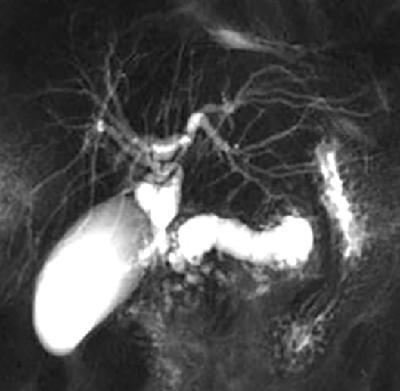

Shrinivas B. Desai, Ritu K. Kashikar, Shreya Shukla Radiological signs are classical and distinctive abnormalities characteristic of a disease. These can be seen on any imaging modality. Resemblance to commonly seen objects and patterns form the basis of radiological signs. The aim is to help the reader associate, understand and memorize these pathologies with the aid of signs. Various signs pertinent to hepatobiliary system are described in the chapter. Described on MRI when liver lesion shows a peripheral rim of high T2 signal intensity with the centre of the lesion appearing isointense to the background of noncirrhotic liver on T2WI mimicking an atoll. It is considered a characteristic sign of an inflammatory hepatic adenoma (image) but is only seen in about one-third of cases Extrinsic smooth impression over medial aspect of duodenum along its posteroinferior aspect, seen in pancreatic head pathologies like carcinoma. This sign is seen in pancreatic adenocarcinoma Presence of a persistently hyperattenuating dot within a lesion on arterial and portal venous CT. This corresponds with peripheral nodular enhancement seen on dynamic MR. Presence of bright dot suggests that the lesion is a hemangioma and helps in ruling out metastasis Ultrasound appearance of multiple cystic spaces or lesions that has been used to describe the appearance of an intraductal papillary mucinous neoplasm of the pancreas. Seen on contrast CT in portal hypertension. The appearance is based on resemblance to Medusa from Greek mythology. Dilated engorged paraumbilical veins radiating across umbilicus to join systemic veins is seen. This sign is seen in Caroli’s disease on contrast CT. Enhancing dots within dilated intrahepatic bile ducts represent portal radicles. Caroli’s disease Irregularly dilated pancreatic duct with multiple strictures and intervening dilatation with associated dilated side ductules resemble multiple lakes supplied by a single territory. Best seen in MRCP images. Chronic pancreatitis It is a finding on MRI and CT and is best seen on MRI T2-weighted and postcontrast T1-weighted sequences. Small necrotic/purulent areas in the pyogenic abscess ‘cluster’ together and then coalesce into a larger necrotic/purulent areas, eventually becoming a larger septated abscess cavity. At the periphery of these clusters: Associated with pyogenic hepatic abscesses and can help differentiate pyogenic abscesses from other types of liver lesions Abrupt termination of gas within the proximal colon at the level of radiological splenic flexure. The inflammatory exudates in pancreatitis extend to the phrenicocolic ligament giving rise to this sign Seen on grey scale ultrasound as a reverberation artifact when small calcific or highly reflective objects are imaged. The colour comet-tail artifact is an ultrasonographic sign seen in a number of situations when colour Doppler scanning is performed. This sign occurs in cases of traumatic right-sided diaphragmatic rupture with resultant partial herniation of liver through the defect. Separation of the herniated liver from its intra-abdominal component is via a small constriction at the level of diaphragm resembling a cottage loaf. Cottage loaf is a particular shape of bread in which larger and smaller roughly spherical balls are squashed together. Traumatic right-sided diaphragmatic rupture with resultant partial herniation of liver Bile eccentrically outlines luminal stone, creating a low attenuation crescent. Best seen on MRCP images. Choledocholithiasis Dilatation of both pancreatic duct and CBD is referred to as the double duct sign. Positive double duct sign suggests the diagnosis of carcinoma of the head of the pancreas and ampullary tumours and is hence considered ominous. Occasionally the sign may be seen in impacted gallstone in the distal duct. This feature is seen in patients with liver abscess on contrast-enhanced CT. A double, inner hyperattenuating and outer hypoattenuating rim is seen surrounding the hypodense abscess. The inner hyperattenuating rim corresponds to the enhancing abscess membrane, while the outer rim corresponds to the edema of the surrounding liver which appears hypodense and may show delayed enhancement. Liver abscess A positive duct penetrating sign is when a mass is penetrated by an unobstructed pancreatic duct; this makes focal pancreatitis the most likely cause rather than pancreatic carcinoma. This sign is best appreciated on MRCP (or ERCP). A radiographic sign that can be useful in differentiating between focal pancreatitis (inflammatory pancreatic mass) from pancreatic carcinoma. The duct-penetrating sign on MRCP is more helpful in differentiating between these two entities than a delayed enhancement pattern on CT or MRI It occurs when there is both limy bile and a gallstone in the common bile duct. The linear vertical radiopaque bile forms the line of the exclamation mark (i.e. !), whilst a more distal calculus forms the ‘dot’ at the end of the exclamation mark. Pathognomonic imaging sign of the rare diagnosis of limy bile on plain abdominal radiography Nonenhancing ruptured lesion with peripheral rim enhancement showing discontinuity from the rest of the liver and protruding from the liver surface is called the enucleation sign. Ruptured HCC Enlargement of the pericholecystic space. One of the signs of liver cirrhosis Can be seen on technetium 99m sulphur colloid scans of the liver and spleen, as well as CT studies. It occurs as a focal area of increased radiopharmaceutical uptake in the medial segment of the left hepatic lobe (segment IV) occurring as a result of SVC obstruction and portosystemic venous shunting between the superior vena cava and the left portal vein via the internal thoracic and paraumbilical veins. The equivalent of this sign may also be seen on contrast-enhanced CT scans as a hypervascular region. Budd–Chiari syndrome causes the hot spot sign in the caudate lobe

7) Chain of lakes